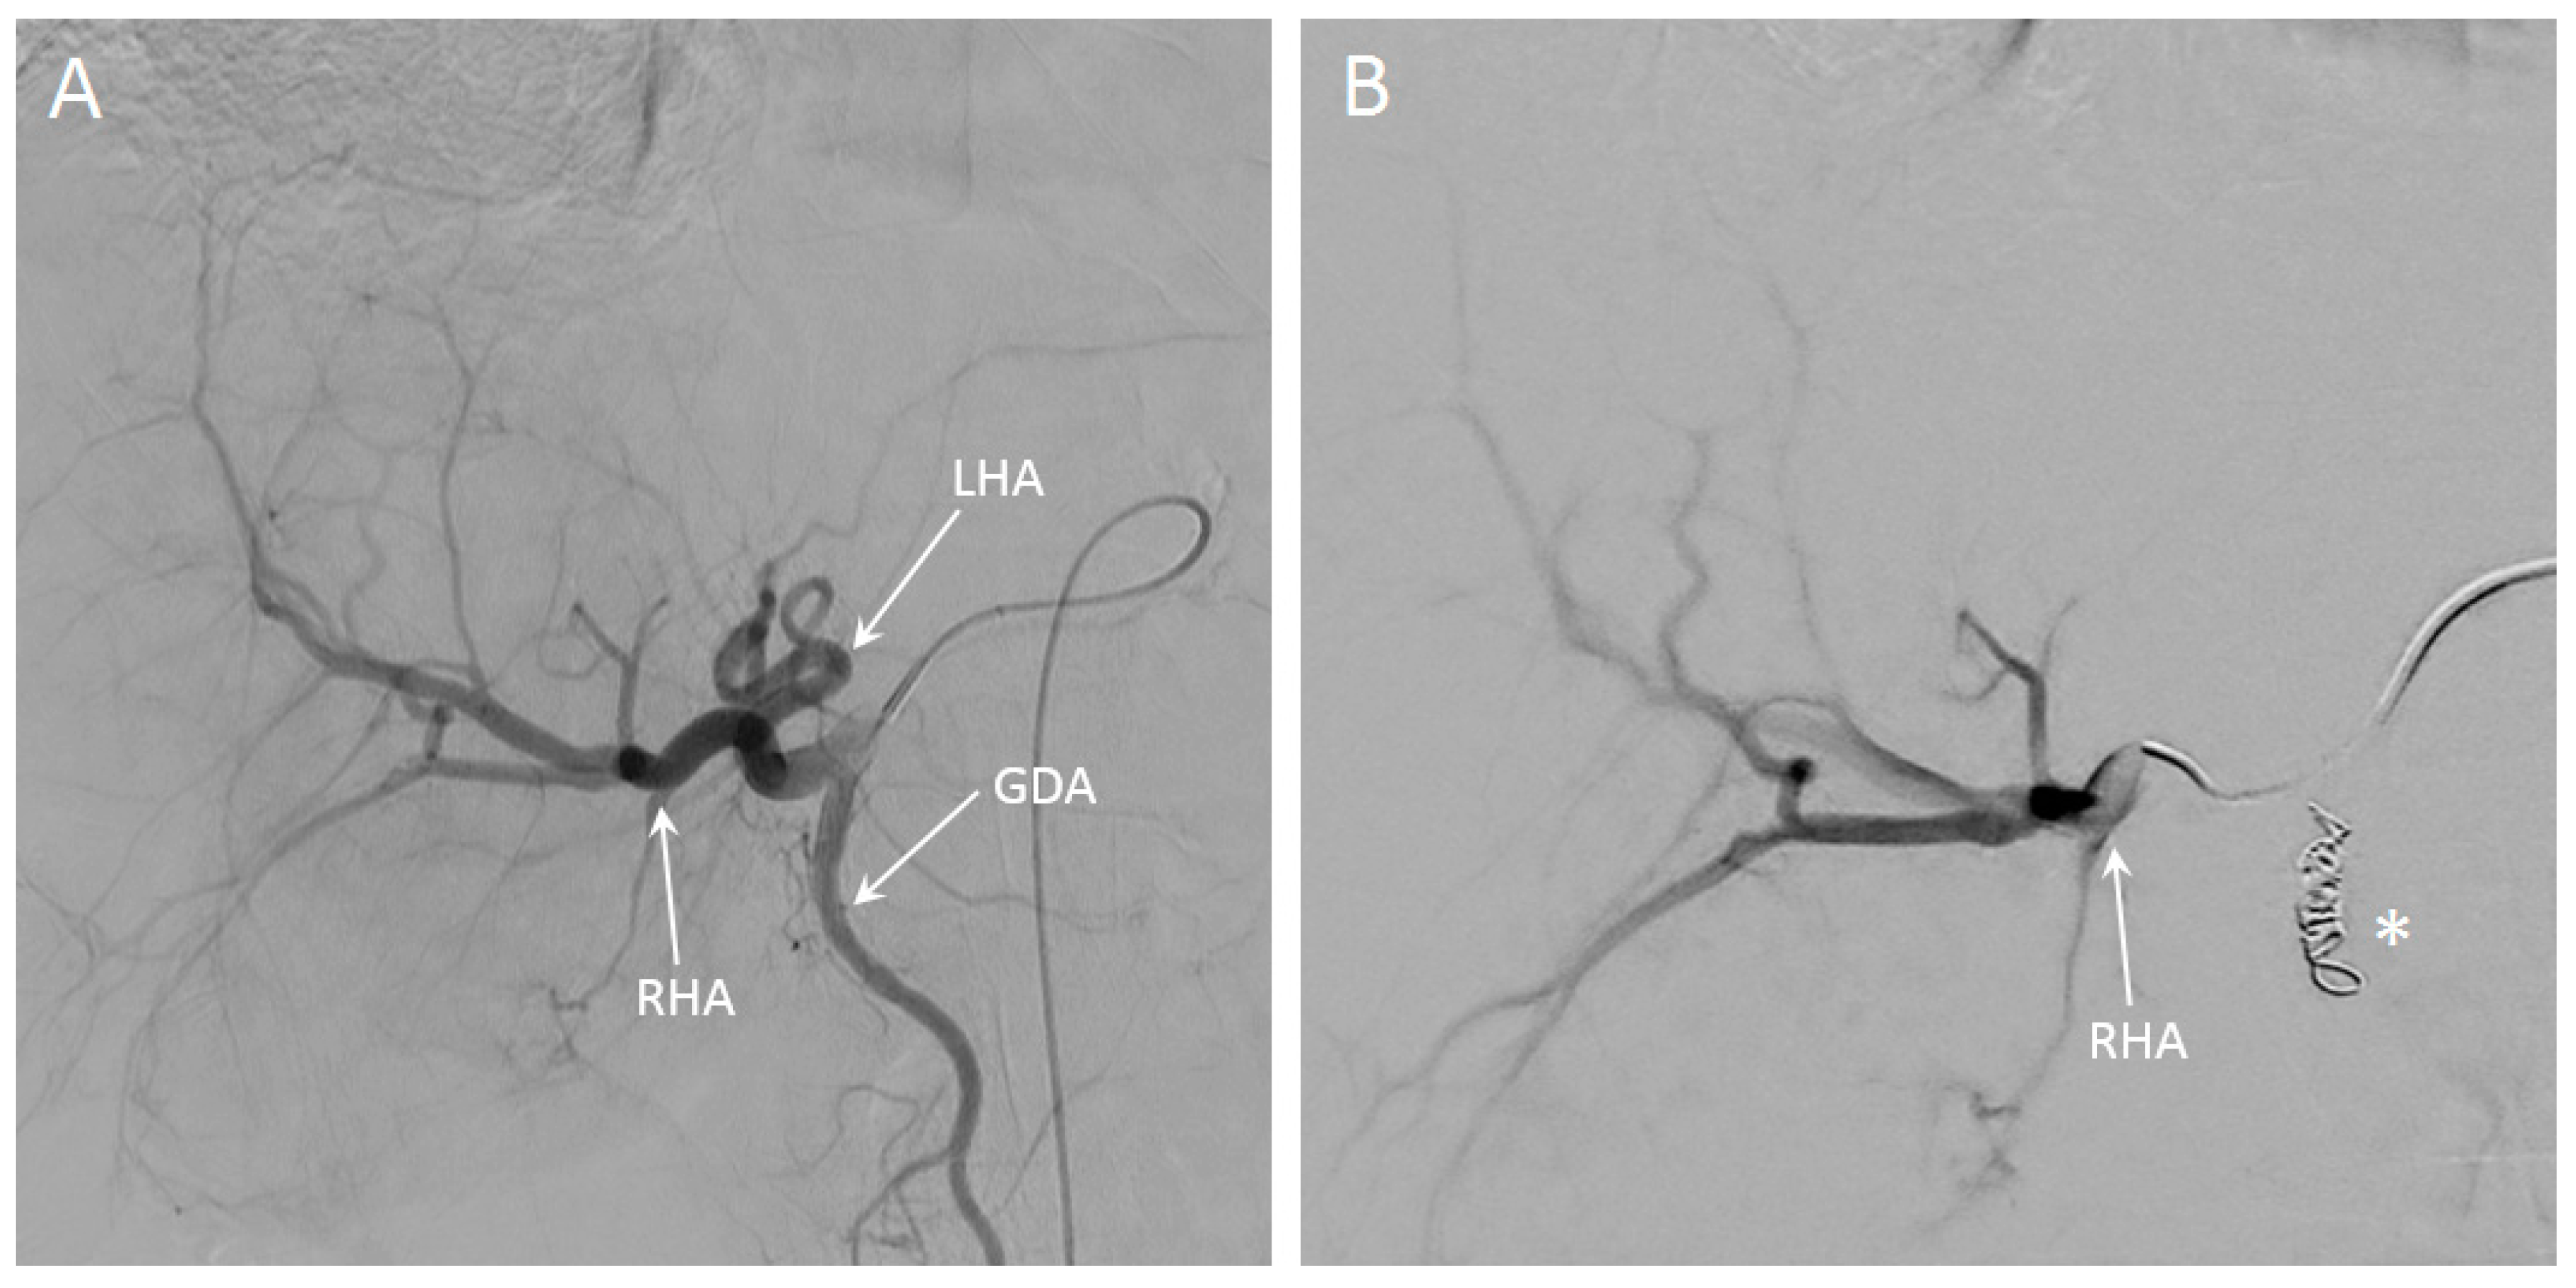

SIRT was performed in a 74-year-old patient with intrahepatic cholangiocarcinoma. The main lesion was located in Couinaud segments 4A and 4B, and there were multiple satellite lesions in all other liver segments (see Figure 9A,B). A whole-liver SIRT was performed under near real-time MR-imaging, starting with the right hemiliver. The microcatheter was positioned proximal in the right hepatic artery (RHA). In Figure 8, angiography of the entire liver and selective angiography of the RHA are visualized. In Figure 9C–F, different chronological frames of the near real-time imaging during the injection of 30% of the total dose of holmium microspheres are presented. A video of this near real-time imaging series is available online (Supplementary Video S1).

Figure 8.

Overview angiography of the entire liver of a patient with intrahepatic cholangiocarcinoma (A), in which the left hepatic artery (LHA), right hepatic artery (RHA) and gastroduodenal artery (GDA) are visible. In (B), the RHA is selectively catheterized, after the GDA has been coiled (indicated with the asterisk).